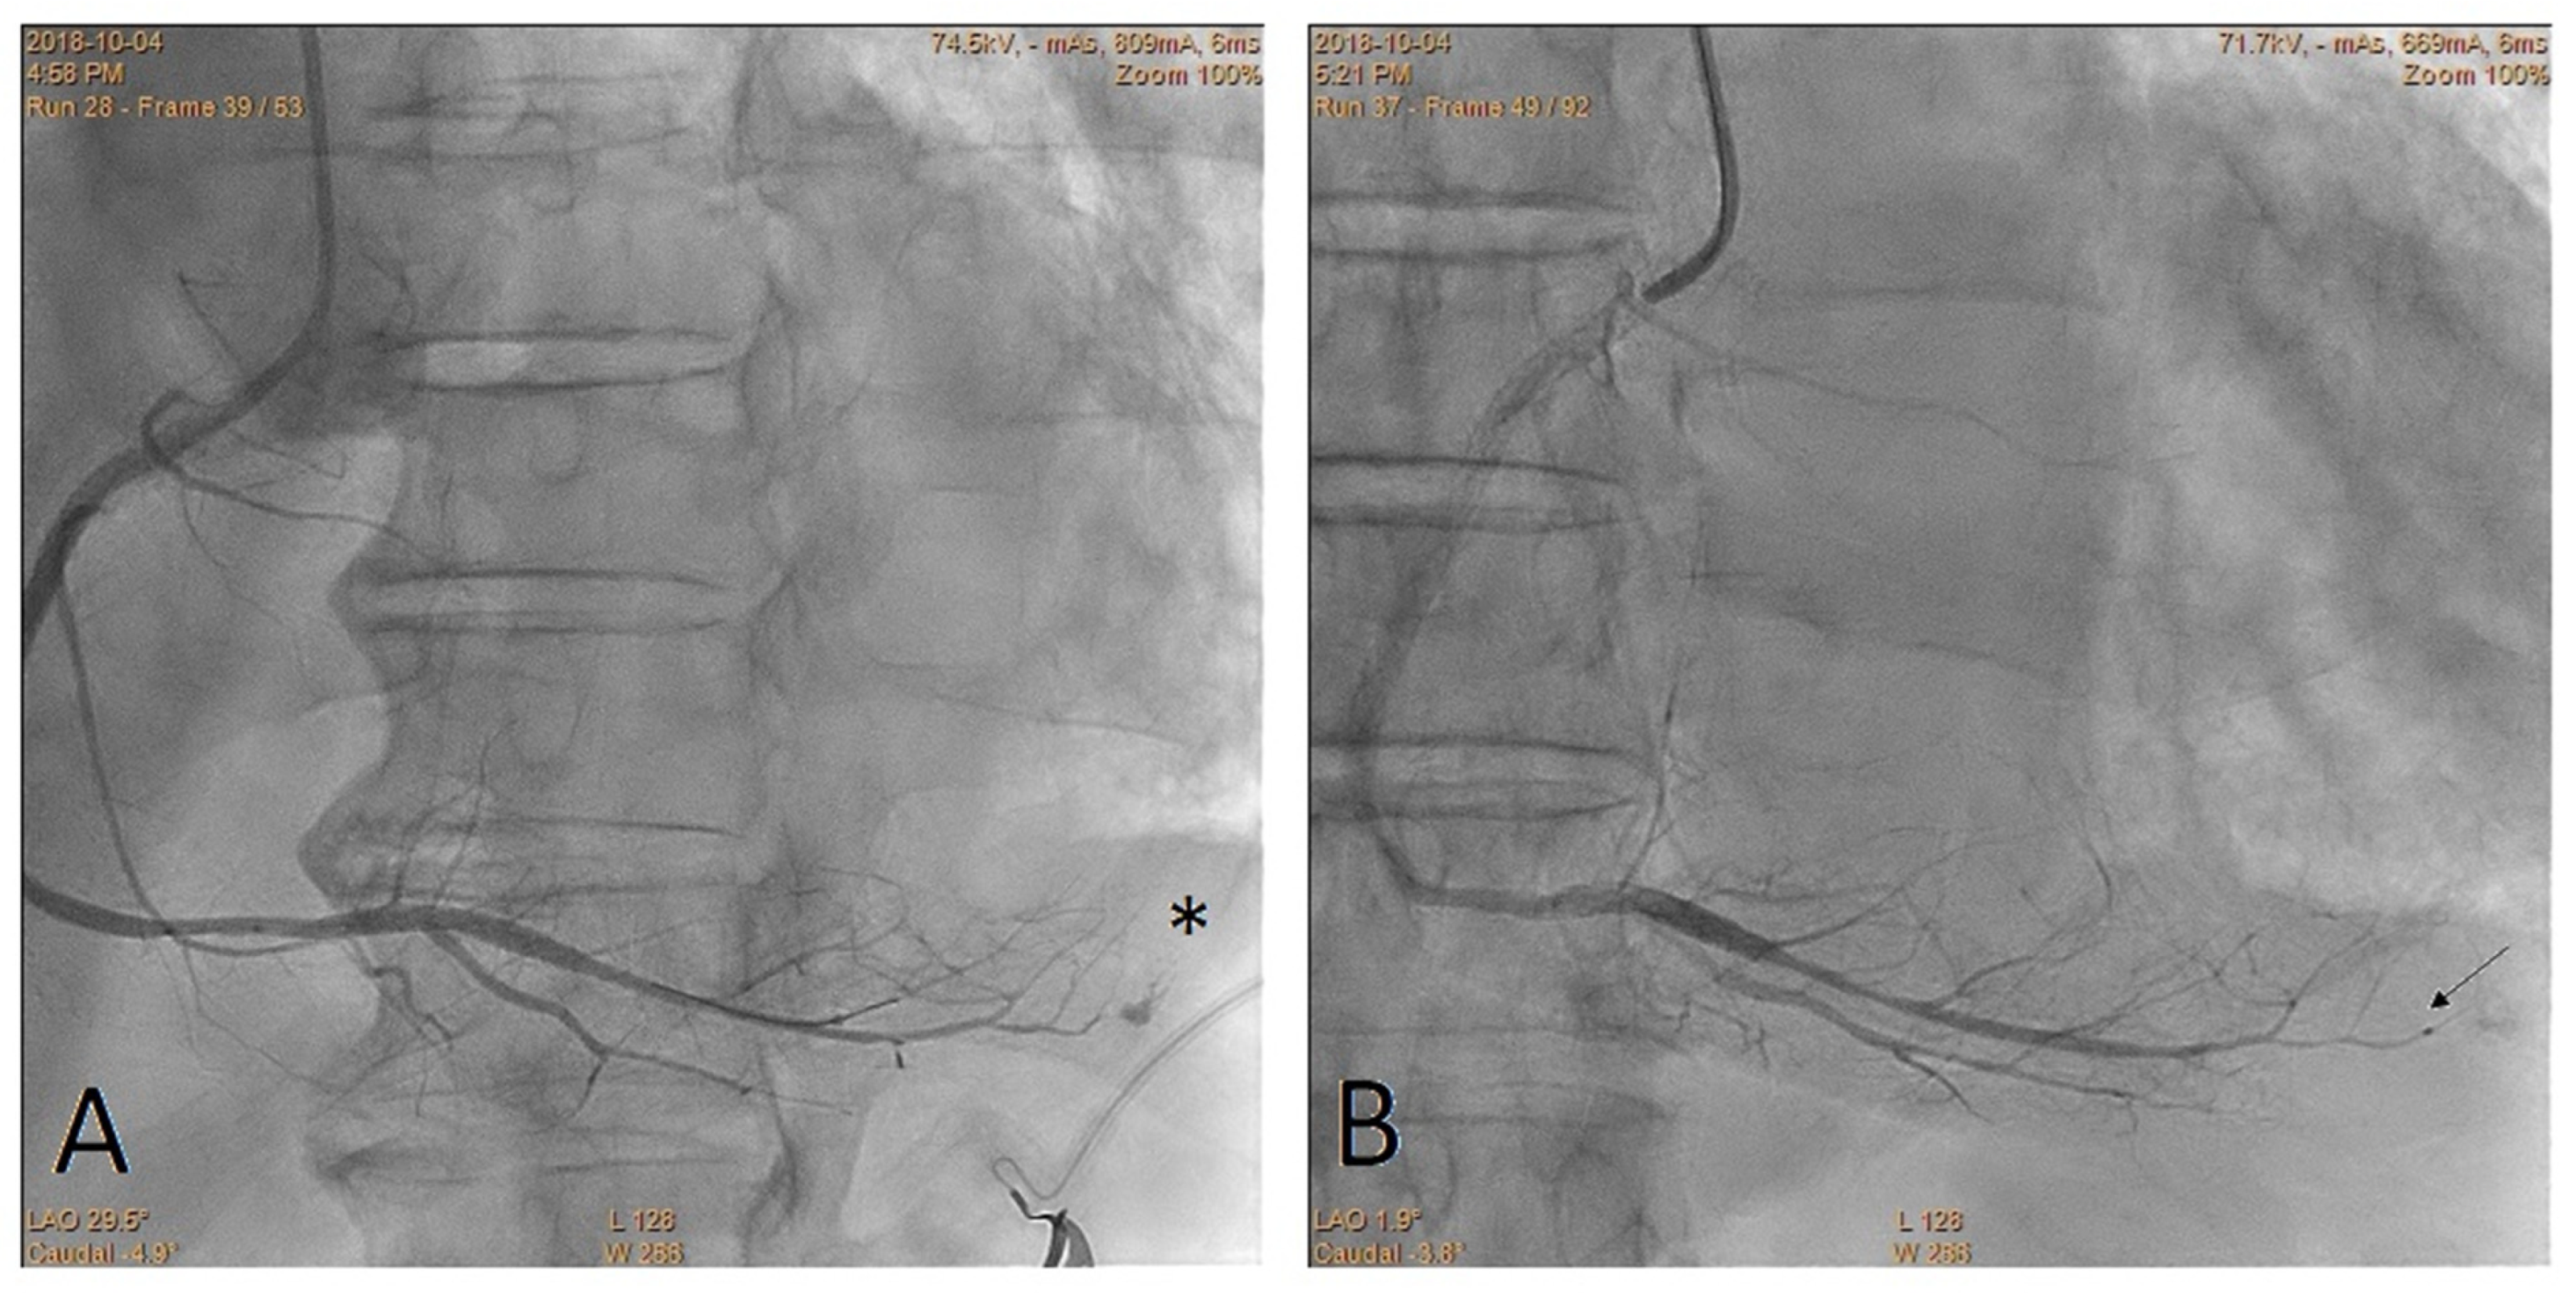

Embolization of Perforated Coronary Artery with a Fragment of Balloon Catheter (Cut Balloon Technique)—Multicenter Study

2. Methods

3. Results